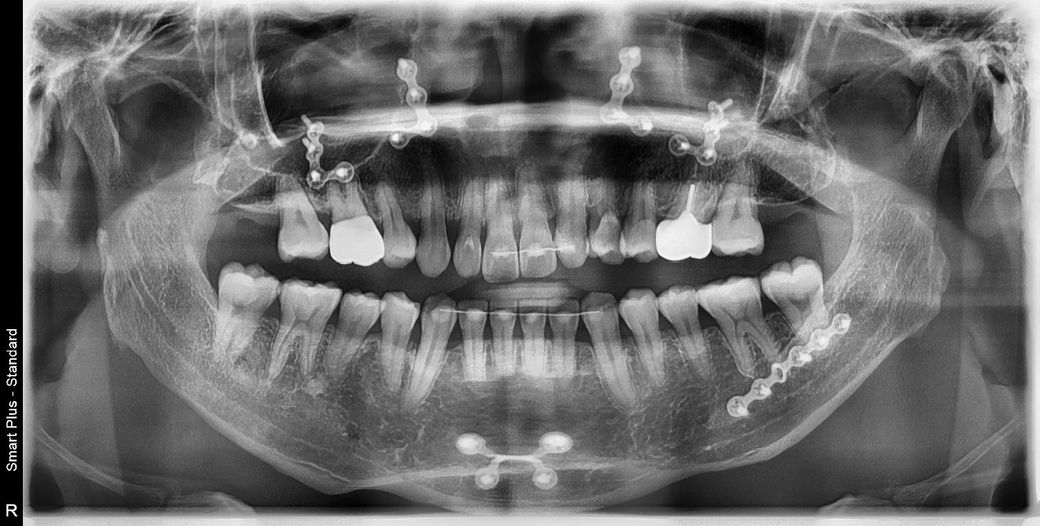

사진을보면 철사가 있을때는 제눈엔 안벌어진걸로보이거든요? 아닌가요? 제 기억에도 안벌어졌었고 철사가있을때 이미벌어져있었다면 그때알았을거고 철사제거할때 더욱 신중했을거거든요

이미 벌어진부분이있는곳에 철사를 완전제거를한다? 말이안되잖아요

• 1번 째 사진